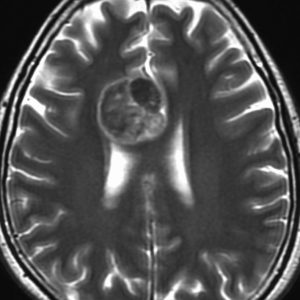

悪性グリオーマと区別しづらい

左はT2強調画像です。内部は壊死にみえますが,転移性脳腫瘍の特徴である周辺脳浮腫がほとんどありません。右のガドリニウム増強では周囲が不規則に造影されます。肺腺癌に特徴的な画像かもしれませんが,膠芽腫との区別が難しく,原発巣もわからず単発ですと生検術が必要になります。FDGでもMet-PETでも脳腫瘍自体は鑑別はできません。FDG-PETで他の臓器に病巣があると転移としていいでしょう。